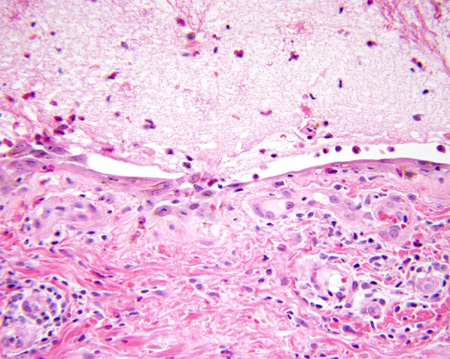

Для диагностики буллезного пемфигоида необходимо провести биопсию кожи, предпочтительно вырезая целый пузырь с небольшой областью соседней незатронутой ткани. Необходимо провести биопсию новообразованного пузыря, стараясь не нарушить целостность и не повредить ткань. Необходимо взять для проведения биопсии и образцы соседней нормальной ткани, стараясь ее не повредить. В продромальной, не буллезной фазе или при нетипичном случае результаты световой микроскопии могут быть менее специфическими и недиагностическими. При высоком подозрении и отрицательных результатах исследование можно повторить. Положительный результат показывает субэпидермальный пузырь с дермальным воспалительным клеточным инфильтратом, содержащий большое количество эозинофилов.[Figure caption and citation for the preceding image starts]: Результат световой микроскопии: субэпидермальный пузырьИз коллекции д-ра Весны Петрон-Росик (Dr Vesna Petronic-Rosic) [Citation ends].